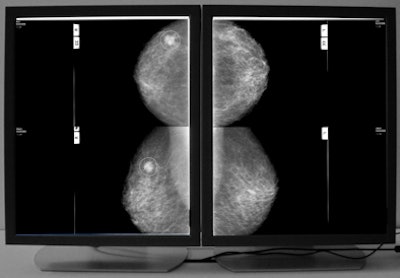

![]() |

| Example of VuCOMP mass detection displayed on a workstation. All images courtesy of Dick Tabbutt and VuCOMP. |